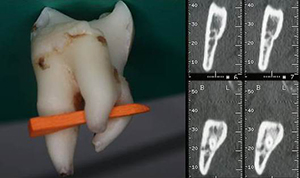

A exodontia de dentes inclusos tanto pode ser uma intervenção cirúrgica simples, rápida e segura, como difícil, demorada e consequentemente com maior morbilidade.

Nos últimos anos não se tem observado uma grande evolução na abordagem cirúrgica dos dentes inclusos para além do aparecimento de melhores meios auxiliares de diagnóstico imagiológico, de equipamentos (piezocirurgia) assim como de técnicas e materiais de regeneração óssea.